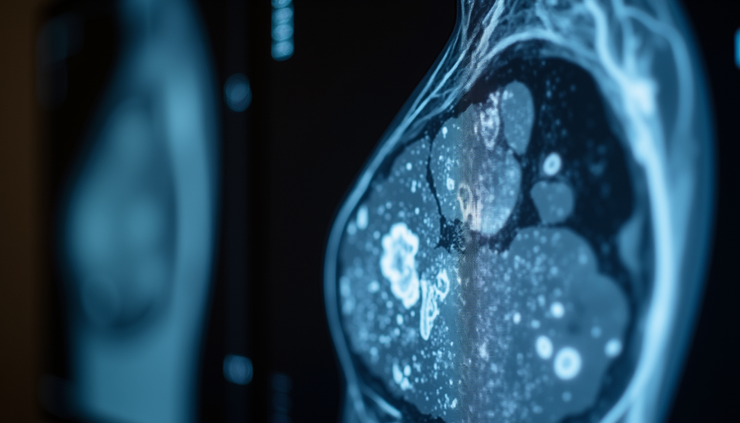

Magnetic Resonance Imaging (MRI)

Recommended for high-risk individuals, such as those with genetic mutations.